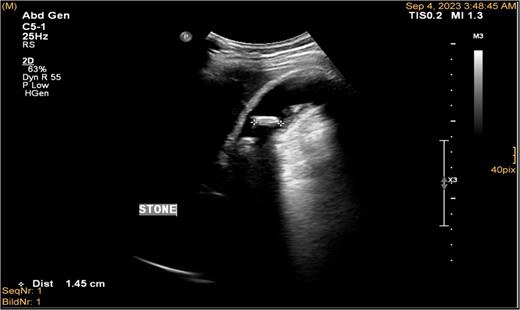

A 41-year-old male with a clear medical background, presented to the Emergency Department with right upper quadrant (RUQ) abdominal pain for two days, associated with fatty dyspepsia, anorexia, nausea, and vomiting. On arrival, his heart rate was 111 bpm with a blood pressure of 128/94 mmHg. On examination, a yellowish discoloration of skin and sclera was noted with a negative murphy sign. Investigations showed elevated liver enzymes (LFT). An initial abdominal ultrasound showed a distended gallbladder with a thickened wall and multiple stones, largest measuring approximately 1.4 cm, and a common bile duct measuring 5 mm (Fig. 1). A magnetic resonance cholangiopancreatography (MRCP) identified a tiny 4-mm mid-cystic duct stone without intrahepatic biliary dilatation. After the initial management, an emergency LC was performed, which posed minimal challenges. Fortunately, no intraoperative complications were reported. A drain was kept in the subhepatic area, and the patient was kept under close observation. Second day postoperatively, the patient experienced dizziness and an intense RUQ pain despite proper analgesia. His heart rate was 89 bpm with a blood pressure of 107/64 mmHg. Investigations showed a drop in hemoglobin level from 13.8 to 9.9 g/dl. An abdominal ultrasound showed a right subcapsular heterogeneous collection with a scalloped liver surface (Fig. 2). Therefore, an initial diagnosis of ISH post-LC was considered. Following the initial fluid resuscitation and blood transfusion, a further decline in hemoglobin level was noted reaching 8.8 g/dl. Further blood transfusion was commenced achieving stabilization. Further CT scan showed subcapsular hepatic hematoma measuring 7.1 × 19 × 21 cm, in its transverse, anteroposterior, and craniocaudal diameters, respectively, with no evidence of active extravasation (Fig. 3) confirming the final diagnosis of ISH post-LC. A multidisciplinary decision was made to continue conservative management after a proper explanation of the potential risk of sudden rupture of hematoma. The patient’s clinical condition and hemoglobin level, in addition to drain output, were meticulously monitored in the general ward, ensuring early detection of deterioration. Four days later, a follow-up CT scan revealed no new significant interval changes (Fig. 4). Nine days postoperatively, the patient was discharged with a follow-up appointment, which showed almost complete resolution.

Ultrasonography demonstrated a distended gallbladder, thickened gallbladder wall measuring 6 mm, with multiple gallbladder stones, the largest one measuring approximately 1.4 cm.